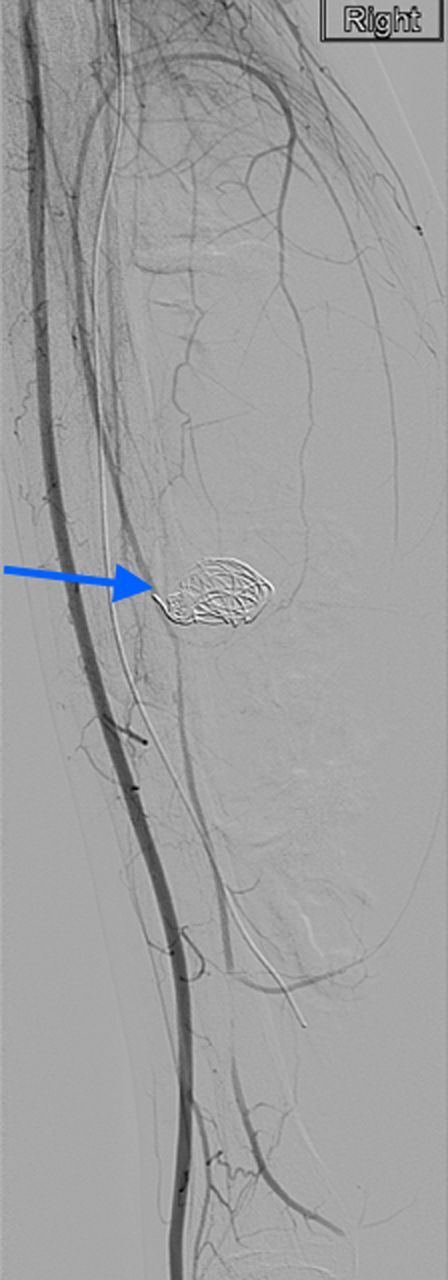

A 20-year-old man with no past medical history presented to the emergency department with non-displaced and closed transverse fracture of the left mid-tibial shaft and an intact fibula induced by a tackle during a football match. On examination, he had no neurovascular deficit and all crural pulses were palpable. His fracture was treated conservatively with a non-weight bearing above knee plaster cast later replaced by a below knee cast for a total period of 6 months. Upon examination during his attendance to the facture clinic, x-ray demonstrated no signs of fracture union. The subsequent magnetic resonance imagining (MRI) confirmed a nonunion of the fracture along with an ovoid 2.7 cm posterior compartment vascularized mass causing bowing of the interosseous septum with no evidence of avascularity of the bony margins (Fig. 1). This was confirmed to be a pseudoaneurysm originating from the PTA. An endovascular approach was adopted, and the pseudoaneurysm was injected with 2 ml of thrombin, filled with multiple coils and deployment of an angiography balloon (in the sac) (4 mm × 6 cm) for 7 min (Fig. 2). This resulted in complete cessation of the pseudoaneurysm with normal flow in the PTA (Fig. 3). The residual extravasated hematoma was later drained by an open approach. Follow-up x-ray (6 months) demonstrated complete union of the fracture site with no associated complications.

Angiographic image, demonstrating the site of the nonunion, coil insertion to the pseudoaneurysm and extravasated contrast.